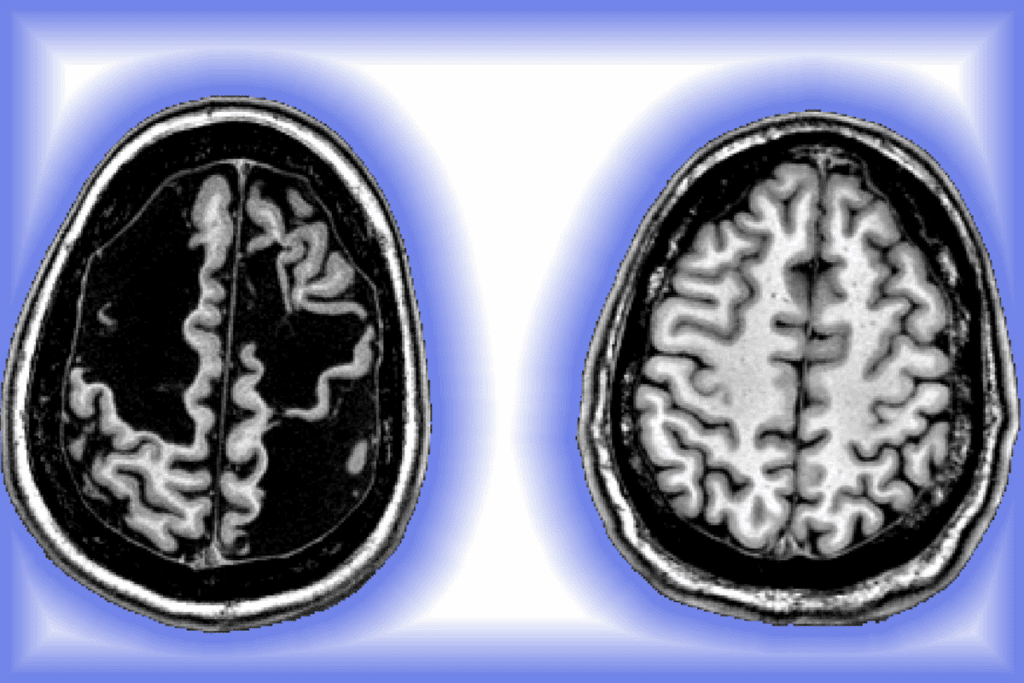

Diagnosis of Brain Metastases from Lung Cancer

Imaging Studies

Imaging is vital for diagnosing brain metastases. MRI and CT scans are the main tools. MRI is very good at finding brain metastases, thanks to contrast agents.

CT scans are used in emergencies or when MRI is not available. They are quicker but not as good at spotting small metastases as MRI.